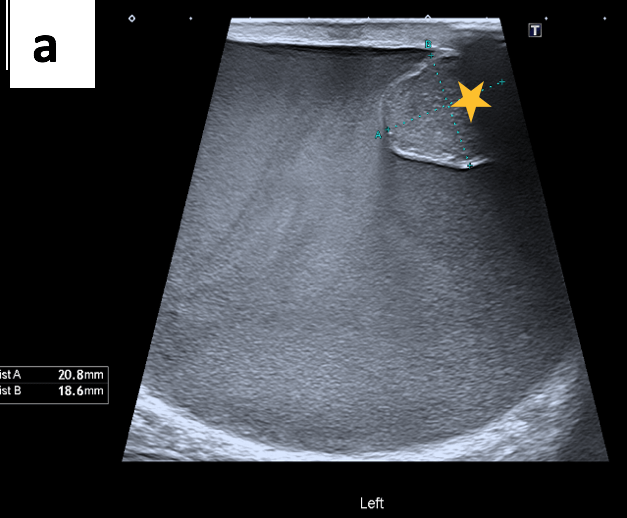

The ultrasound scan revealed turbid fluid with internal echoes and multiple hypoechoic, nodular, excrescences/adherent lesions on the tunica vaginalis. MRI scan was unremarkable.

Ultrasound is the primary imaging modality used to assess scrotal swelling or potential tumours. This is due to its easy availability, use of non-ionising radiation, cost-effectiveness and real-time features. However, ultrasound is highly operator-dependent and, therefore, requires adequate training. Other modalities, such as magnetic resonance imaging (MRI) or computed tomography (CT), can be considered when ultrasound findings are equivocal. Histology analysis of surgically removed (or biopsied) scrotal tumours is the gold standard for diagnosis. Although rare, tumours of the tunica vaginalis include fibrous pseudotumours and malignant mesotheliomas. They both primarily affect middle-aged men and are characterised by painless nodules and scrotal enlargement. The common sonographic appearance suggestive of MMTV includes the presence of singular or multiple painless nodules/excrescences in the tunica vaginalis with hydrocele. The diagnosis in this case was confirmed through orchiectomy followed by histopathology and immunochemistry.